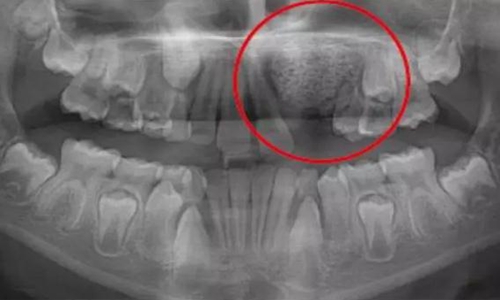

一名 23 區(qū)的9歲患者,在診所接受檢查時(shí)發(fā)現(xiàn)口內(nèi)中存在大范圍含牙囊腫[圖1]。由于上頜竇下沿出現(xiàn)大范圍突出,迫切需要接受囊腫去除手術(shù)[圖2和3]。

囊腫去除后的大量骨缺損[圖3]